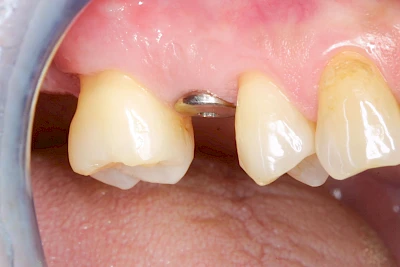

Implantate: Bestandteile

Implantate sind künstliche Zahnwurzeln. Nach einer gewissen Einheilzeit im Knochen (meist 3-6 Monate) erfolgt über einen separaten Aufbau (Abutment) die Befestigung einer Krone bzw. Brücke oder Zahnprothese.

In seltenen Fällen sind Implantate samt Aufbau aus einem Stück gefertigt. Auch gibt es Situationen, die ein Früh- oder sogar eine Sofortbelastung erlauben – dann kann die Einheilzeit der Implantate in den Knochen verkürzt oder sogar gänzlich darauf verzichtet werden.

"Stiftzahn" und "Implantat" ist nicht dasselbe! Bei einem Stiftzahn wird die Zahnkrone mit einem Stift in die noch vorhandene eigene Zahnwurzel zementiert. Ein Implantat im Gegensatz dazu ist selbst die (künstliche) Zahnwurzel, die dann weiter mit einem Zahnersatz versorgt wird.